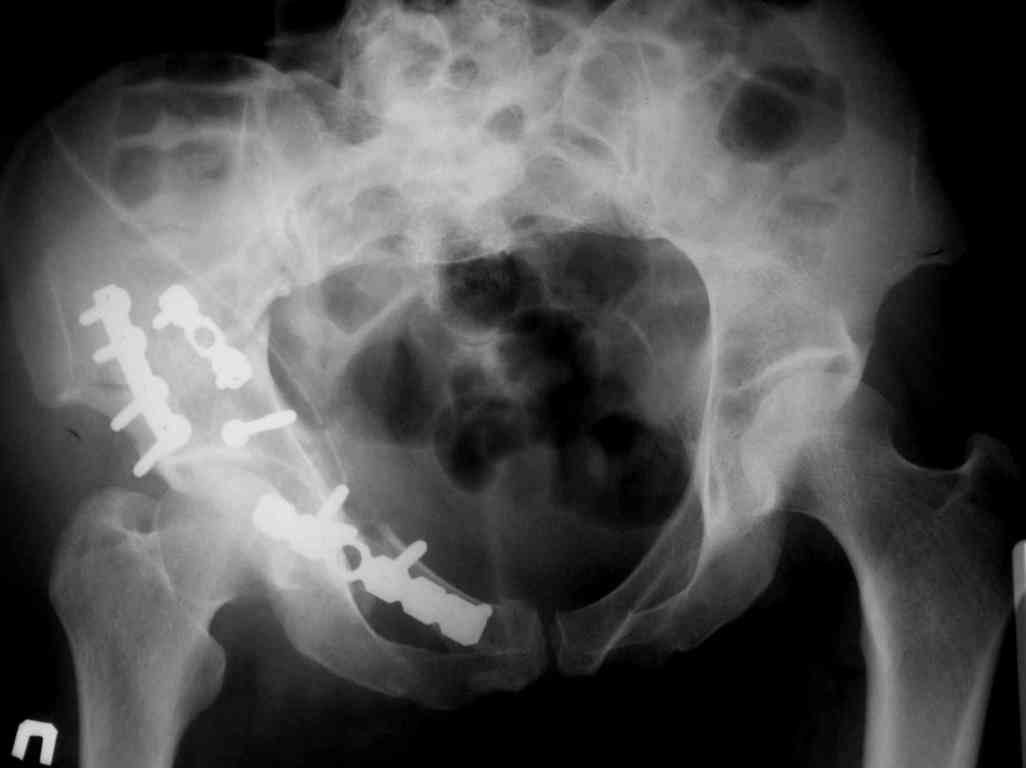

P.S. в приложении R пациентки с похожей проблемой доступа.. за исключением того, что перелом

двухколонный. Вертлугу лечили Y доступом.

Я предпочитаю в таких случаях расшириться Y-образно, и тогда этих проблем просто нет, тем более, что в этом случае головка извлекается мягко, не царапается хрящ, и репозиция лонноседалищного фрагмента идет сначала через перелом (банальным крючком) и лишь затем из седалищной вырезки (так спокойнее за седалищный нерв).